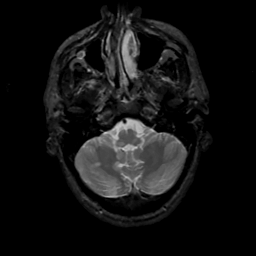

MR Study #8, March 31, 1991 -- Slice #9

[Home][Help][Clinical][Tour 1][Tour 2] Slice 9